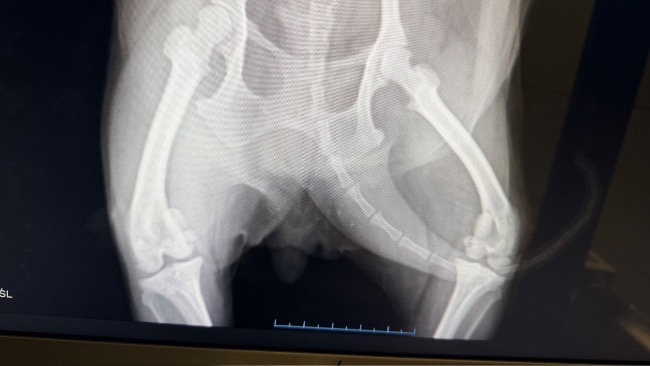

Tina kuleje. Każdy krok sprawia jej ból. Potrzebuje pilnej konsultacji ortopedycznej, bo jej kolano może być poważnie uszkodzone. Ona nie chodzi swobodnie, ona walczy o każdy ruch.